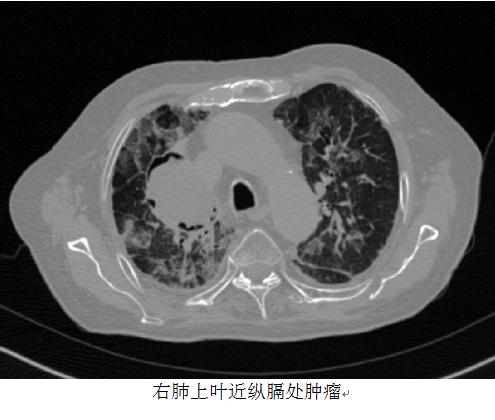

2017年3月,CT所见:右肺上叶近纵膈处可见一个最大截面约4.7cm×6.3cm的软组织肿块,病灶边缘毛刺,其内密度较均匀,增强后病灶轻度强化,临近支气管开口受压;双肺内可见散在可见斑片样、条索样及磨片玻璃样高密度改编,以右肺上叶为著;双侧胸腔内未见明显液体密度区;纵膈内未见明显肿大淋巴结显示;心包略增厚。